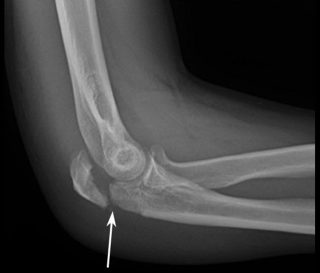

В дальнейшем пострадавшего направляют на рентгенографию, чтобы визуализировать анатомические структуры, определить наличие или отсутствие отломков, смещений. Как правило, дополнительные обследования не нужны, однако для изучения состояния плотных тканей может потребоваться КТ, МРТ локтевого сустава. Если перелом сопровождается повреждением локтевого нерва, пациента консультирует невролог.